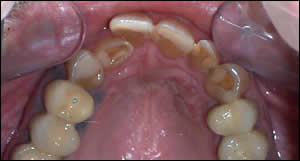

Fig 7: Occlusal views demonstrate the defective restorations, enamel abrasion, and crooked teeth. It was decided that treatment would be restricted to the anterior teeth. A multi-disciplinary approach was essential in achieving a successful functional and esthetic result.